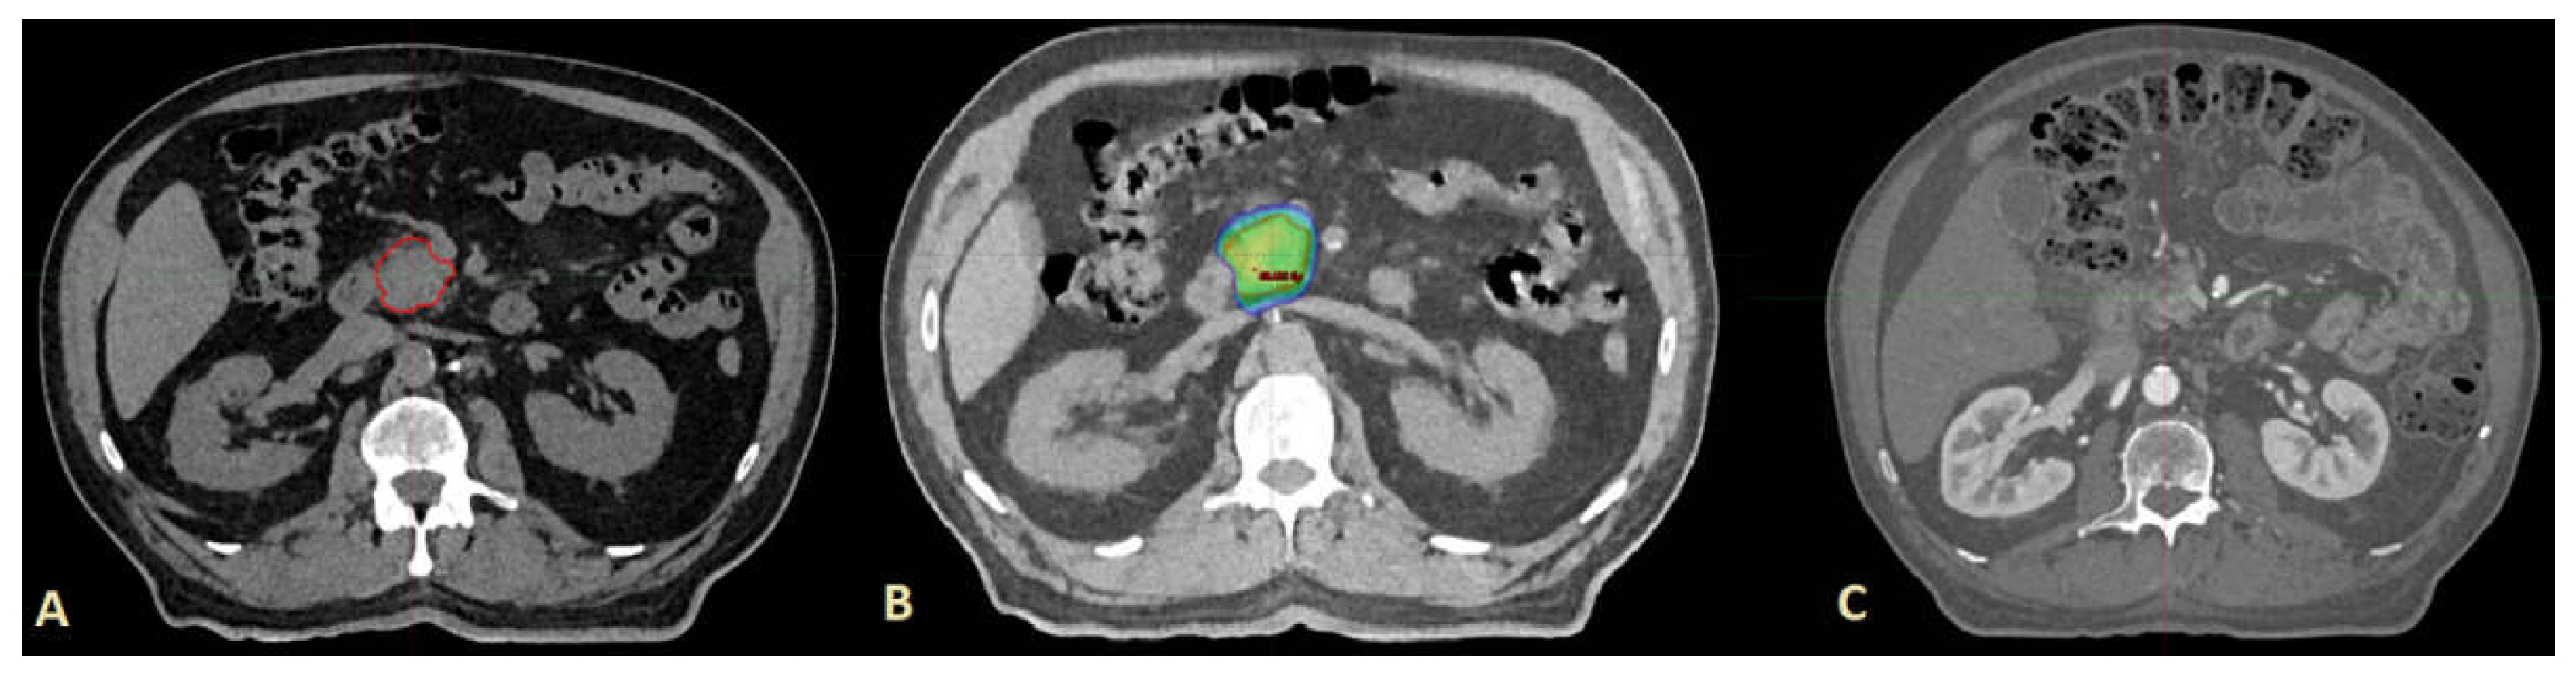

2.4. Stereotactic Ablative Radiotherapy

- For the patients that were treated in FB:

- The planning 4D-CT in a late exhale phase was used and coregistered with MRI.

- CTVs were delineated on the T1 or T2 images of the MRI, with further corrections (if needed) on phase-gated 4D-CT scans.

- For the patients that were treated in DBH:

- The planning MSCT in DBH was used and coregistered with MRI.

- CTVs were delineated on the T1 or T2 images of the MRI, with further corrections (if needed) on MSCT scans in DBH.

- For the patients treated in DBH we used planning MSCT in DBH for coregistration with cone beam CT (CBCT)

- For the patients treated in FB we used planning 4D-CT reconstructed in all breathing phases (“Average intensity projection”) for coregistration with CBCT.